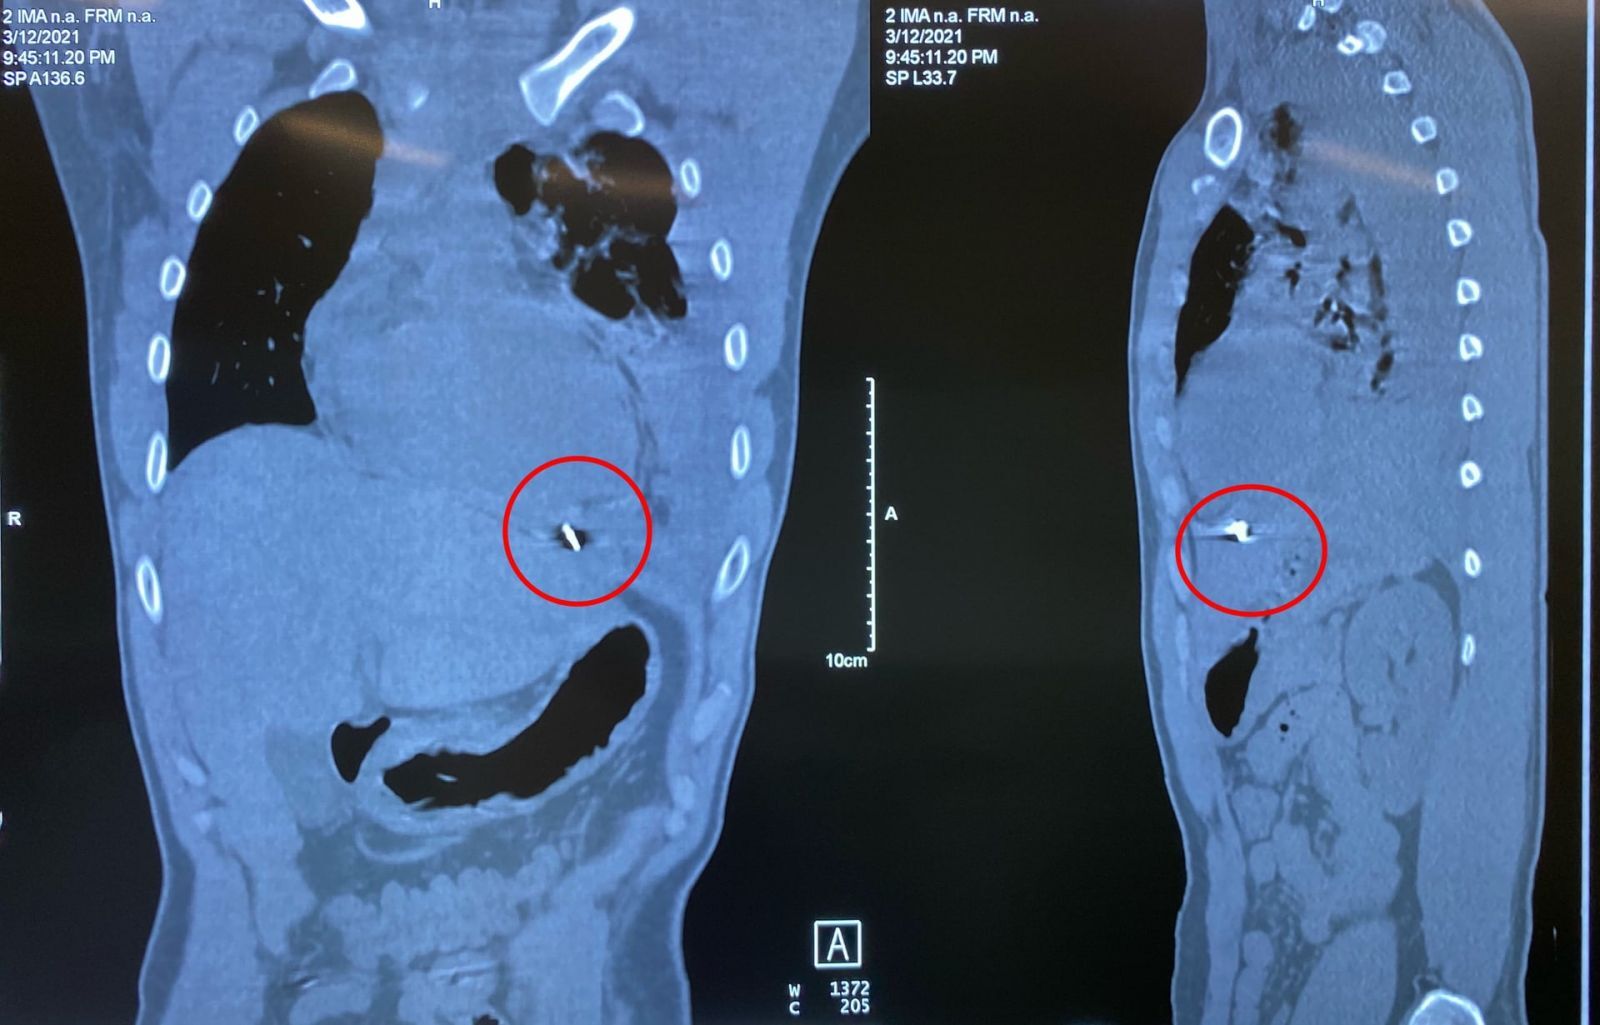

Bệnh nhân được chuyển đến Bệnh viện 108 trong tình trạng khó thở cả hai thì, nhịp tim nhanh, huyết áp xu hướng tụt thấp. Bệnh nhân được thở ô-xy, theo dõi sát tình trạng hô hấp, đồng thời khảo sát bằng siêu âm và chụp CT lồng ngực: phát hiện tràn máu màng phổi trái mức độ nhiều, kèm theo xẹp phổi trái thụ động, có mảnh kim khí nằm trong cơ hoành, mặt dưới tâm thất trái.

Các bác sĩ đã tiến hành phẫu thuật mở ngực đường bên vào khoang màng phổi trái. Trong khoang màng phổi trái và màng tim có gần 1.500ml máu và máu đông. Dị vật là một mảnh kim khí dài khoảng 1cm có cạnh sắc, làm rách mặt trước màng tim và găm vào mặt hoành của màng tim. Tâm thất trái đè lên dị vật và bị cạnh sắc của dị vật cứa rách gây chảy máu vào khoang màng tim và qua lỗ thủng mặt trước màng tim tràn vào khoang màng phổi trái.

Mảnh kim khí nằm trong cơ hoành, dưới tim và ngay trên gan trái của bệnh nhân.